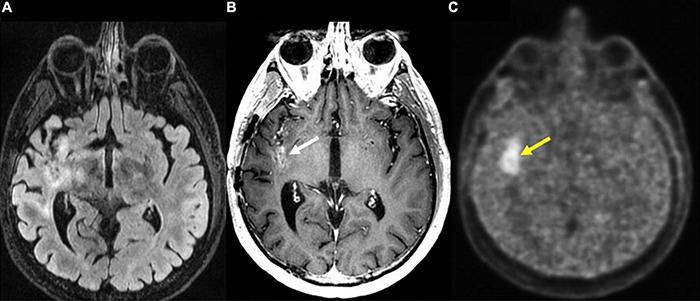

Management of gliomas following initial diagnosis requires thoughtful presurgical planning followed by regular imaging to monitor treatment response and survey for new tumor growth. Traditional MR imaging modalities such as T1 post-contrast and T2-weighted sequences have long been a staple of tumor diagnosis, surgical planning, and post-treatment surveillance. While these sequences remain integral in the management of gliomas, advances in imaging techniques have allowed for a more detailed characterization of tumor characteristics. Advanced MR sequences such as perfusion, diffusion, and susceptibility weighted imaging, as well as PET scans have emerged as valuable tools to inform clinical decision making and provide a non-invasive way to help distinguish between tumor recurrence and pseudoprogression. Furthermore, these advances in imaging have extended to the operating room and assist in making surgical resections safer. Nevertheless, surgery, chemotherapy, and radiation treatment continue to make the interpretation of MR changes difficult for glioma patients. As analytics and machine learning techniques improve, radiomics offers the potential to be more quantitative and personalized in the interpretation of imaging data for gliomas. In this review, we describe the role of these newer imaging modalities during the different stages of management for patients with gliomas, focusing on the pre-operative, post-operative, and surveillance periods. Finally, we discuss radiomics as a means of promoting personalized patient care in the future.

胶质瘤初诊后的管理需要进行周全的术前规划,随后定期进行影像学检查,以监测治疗反应并探查新的肿瘤生长情况。传统的磁共振成像(MR)模式,如T1增强序列和T2加权序列,长期以来一直是肿瘤诊断、手术规划及治疗后监测的主要手段。虽然这些序列在胶质瘤的管理中仍不可或缺,但成像技术的进步使得对肿瘤特征的刻画更加详细。诸如灌注成像、扩散加权成像、磁敏感加权成像等先进的MR序列,以及正电子发射断层显像(PET)扫描,已成为指导临床决策的重要工具,并提供了一种非侵入性方法,有助于区分肿瘤复发和假性进展。此外,这些成像技术的进步已延伸至手术室,有助于使手术切除更安全。尽管如此,手术、化疗和放疗仍使胶质瘤患者的MR图像变化解读变得困难。随着分析和机器学习技术的进步,放射组学在解读胶质瘤成像数据方面具有实现更具定量性和个性化的潜力。在本综述中,我们描述了这些更新的成像模式在胶质瘤患者不同管理阶段的作用,重点关注术前、术后及监测期。最后,我们讨论放射组学作为未来促进个性化患者护理的一种手段。